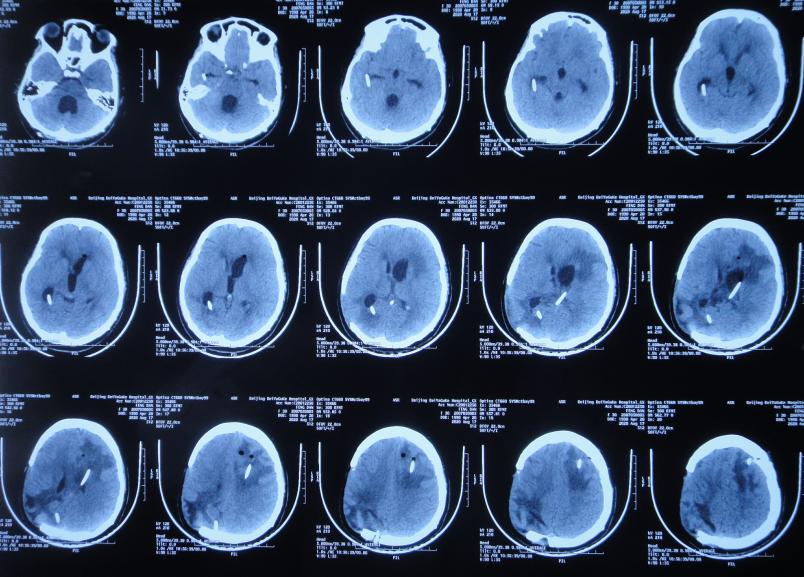

开颅术后15天即2020年4月17日(腰大池引流术后7天),查头颅CT示仍脑膨出( 图-4 ),因腰大池引流管堵塞,给予拔除并第2次重新置换腰大池。

图-4: 2020年4月17日头颅CT

第2次重新置换腰大池引流管后3天即2020年4月20日(开颅术后18天,腰大池持续引流10天),腰大池引流管再次脱出,于是第3次重新放置腰大池引流管。

第3次重新放置腰大池引流管后3天即2020年4月23日(开颅术后21天,腰大池持续引流13天),引流管第4次脱出,因仍间断发热改为每日腰穿1次,并鞘内注射药物。

开颅术后26天2020年4月28日(腰大池引流管第4次脱出后5天),复查头颅CT发现幕上脑室系统扩张( 图-5 );但因患者症状好转,可在搀扶下独立行走,未予处理。

图-5: 2020年4月28日头颅CT